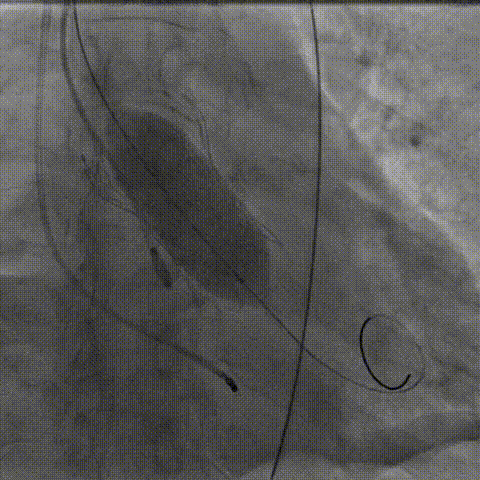

手术影像:

主动脉根部造影

工作位造影